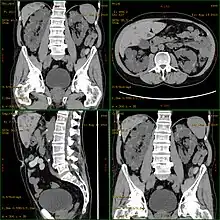

| Severely affected polycystic kidneys removed at time of transplantation | |

| Diagnostic method | MRI, CT scan, Ultrasound[1] |

Polycystic kidney disease can be ascertained via a CT scan of abdomen, as well as an MRI and ultrasound of the same area.[23] A physical exam/test can reveal enlarged liver, heart murmurs and elevated blood pressure.[1]